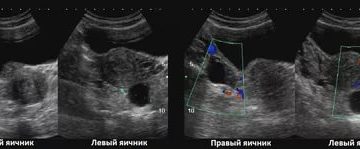

Киста яичника на УЗИ Яичники — это парные органы, имеющие огромное значение при зачатии. Именно…